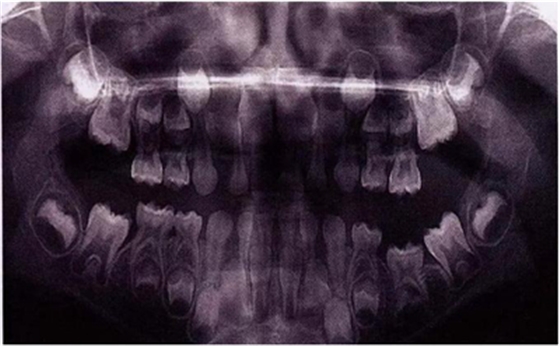

X線片還會(huì)顯示合平面呈現(xiàn)出一個(gè)臺(tái)階,并通常會(huì)有一個(gè)角度朝向固連牙的角型牙槽骨缺損。(圖5)。許多臨床醫(yī)生更愿意選擇拍攝曲面體層片而不是根尖片,因?yàn)榭紤]到乳牙下沉經(jīng)常會(huì)雙側(cè)發(fā)生并合并其它發(fā)育異常,同時(shí)也為了確定是否需要正畸治療。臨床檢查和影像學(xué)檢查聯(lián)合評(píng)估同樣也為了排除其它病因,譬如原發(fā)性的萌出障礙,牙齒嵌入或者其它異常。

圖8展示了一張5歲孩子右下第二乳磨牙嚴(yán)重下沉的口內(nèi)像。臨床檢查可見右下第一乳磨牙遠(yuǎn)中傾斜,朝向下沉乳牙。X線片檢查顯示所有恒牙胚都存在(圖9)。無論是臨床還是影像學(xué),都可檢查到有齲齒的存在。鑒于這顆下沉乳牙在年齡較小時(shí)就已經(jīng)非常嚴(yán)重,同時(shí)還患有齲病,因此決定予以拔除。后期在放置間隙保持器的同時(shí)還應(yīng)持續(xù)觀察監(jiān)測(cè)右下第一恒磨牙和第二前磨牙的萌出情況。

圖9:一名五歲患兒右側(cè)下頜第二乳磨牙嚴(yán)重下沉的曲面體層片